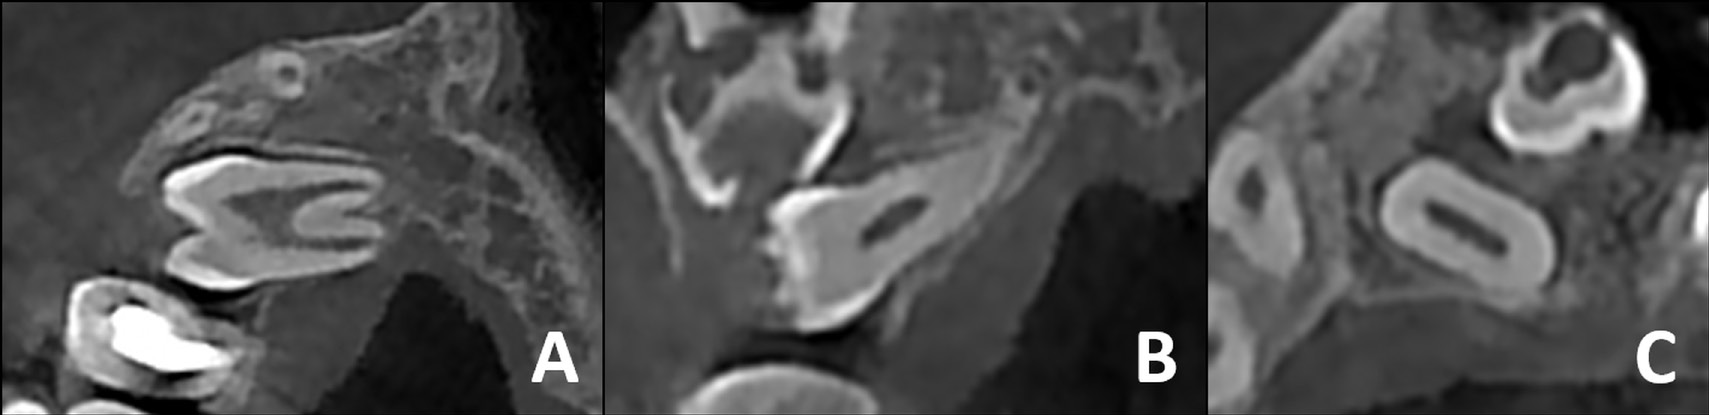

All CBCT images were acquired using a NewTom 5G unit (QR, Verona, Italy) in a standard mode, with a field of view of 12 cm × 8 cm and a voxel size of 250 μm. The kVp and mA values were derived from images obtained through the use of a preview mode. The CBCT images were also examined in terms of the established criteria (Figure 2). Subsequently, a study group was formed.

To measure pulp volume from the CBCT data, a threshold for soft tissue value was set, and the mask creation and segmentation technique was used to determine the contour of the pulp and pinpoint the value of the volume. First, a mask was created to form the pulp chamber and hard tissue segments of each involved tooth. Second, the optimal separation grayscale threshold was selected, which exhibited the pulp chamber within the tooth in all sections and planes (i.e., axial, coronal and sagittal). Third, for the 3D calculation, regions that did not correspond to the pulp cavity were approximately identified and deleted. Fourth, manual erasing and corrected drawing were performed to remove bone fragments at the root and in surrounding teeth at the crown level. Standardization was achieved using fixed threshold values in all teeth. Lastly, with the mask representing the pulp chamber in all planes and sections, an image was generated to calculate the pulp volume. The image value was automatically measured by the software, and the pulp volume was obtained (Figure 3).